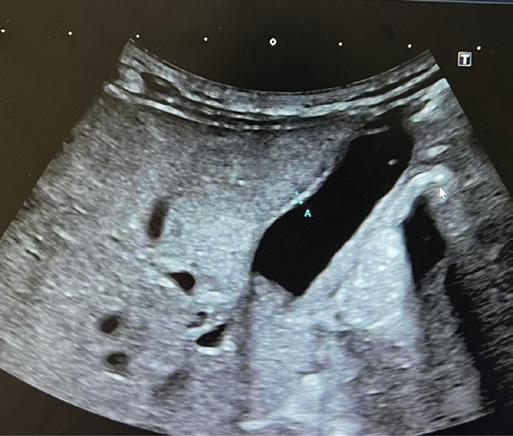

T. è una bambina nata prematura a 32 settimane. Trasferita in TIN per distress respiratorio da aspirazione meconiale, viene trattata con fototerapia per la scoperta di iperbilirubinemia. A causa della persistenza dell’ittero esegue esami del sangue per escludere patologie infettive, tiroidee e deficit di cortisolo. Screening neonatale e indici di emolisi negativi. Dosaggio dell’alfa-1 antitripsina normale [1]. Viene dunque trasferita presso il reparto di epatologia del Necker di Parigi per le cure del caso. Gli esami evidenziano una colestasi a GGT elevate e citolisi epatica (AST 227 U/L, ALT 202 U/L, GGT 516 U/L, BT 8,5 mg/dl BC 7,6 mg/dl). All’ecografia epatobiliare eseguita a digiuno da 6 h si evidenzia una colecisti non atresica [Figura 1], anzi, piuttosto distesa con all’interno sludge biliare, dilatazione della via biliare extraepatica [Figura 2] con evidenza di calcolo a livello della porzione distale coledocica [Figura 3] e dilatazione delle vie biliari intraepatiche, che presentano un aspetto irregolare. Assenza di polisplenia. Davanti alla presenza di un calcolo incuneato, viene avviata terapia iperidratante con aggiunta di UDCA, supplementazione vitaminica ADEC e vit K ev [2]. All’ecografia di controllo non si evidenzia più la litiasi biliare. Nuovo ricovero dopo 6 giorni per la persi-

Figura

Figura 1. Colecisti non atresica distesa con all’interno sludge biliare.

Figura 2. Dilatazione dilatazione della via biliare extraepatica di 6 mm.

Figura 3. Calcolo incuneato a livello della porzione distale coledocica.